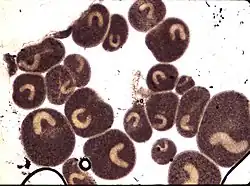

Macroscopically visible trophonts (white spots) on skin or fins is often the basis for a tentative diagnosis of I. multifiliis infection. The diagnosis can be confirmed by microscopic examination of skin and gill smears. Scrapings of skin, fins or gill surfaces (using a cover slip or scalpel) and subsequent mounting on a microscope slide with a few drops of water under a cover slip should be examined under the light microscope (20-400 x magnification). The trophont is slowly rotating, covered by rapidly beating cilia and has a prominent, horseshoe-shaped macro-nucleus. Molecular diagnosis can be based on knowledge of genes encoding the parasite's i-antigen[13] and is performed by PCR and quantitative real-time PCR.